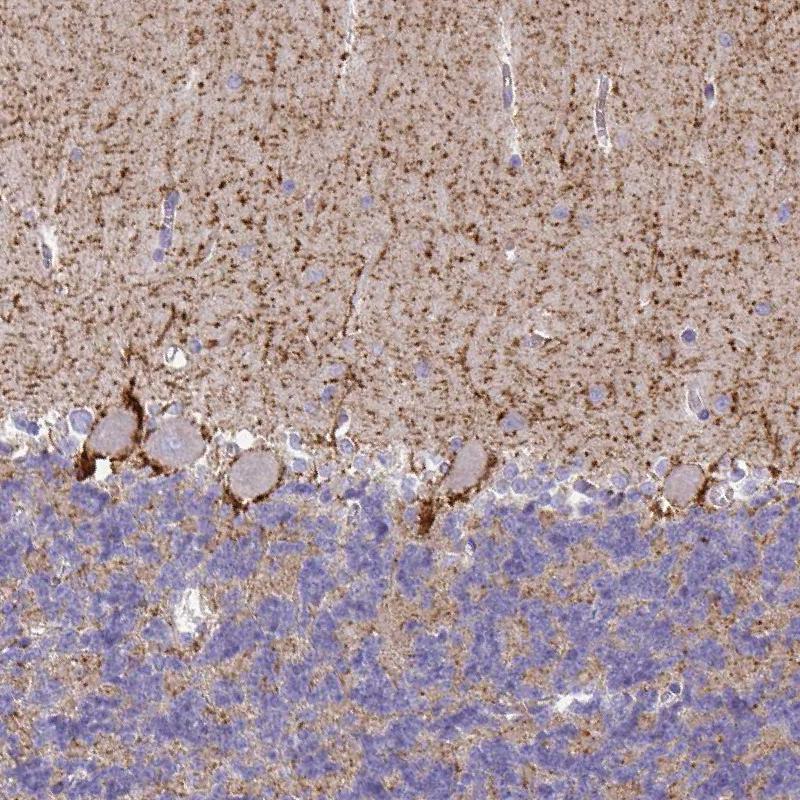

Immunohistochemical staining of human cerebellum shows moderate to strong membranous positivity in neuropil of molecular layer and in Purkinje cell layer.